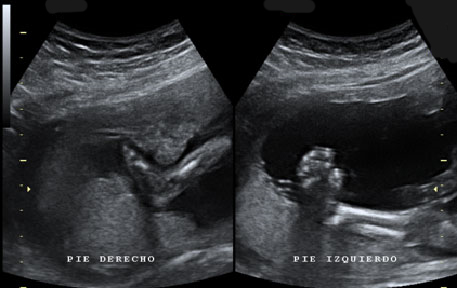

En la imagen ecográfica podemos ver el corte de la cabeza fetal donde se muestra la medición de un ventrículo cerebral aumentado de tamaño (o ventriculomegalia).